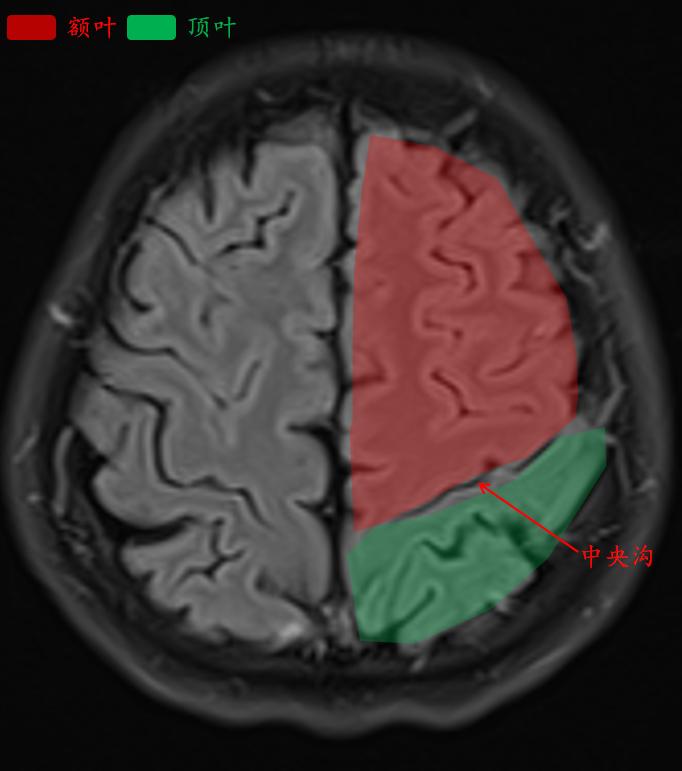

这就是常规医院扫描的t2-flair的相似层厚层间距的图像。

中央沟是额叶和顶叶的分界线。